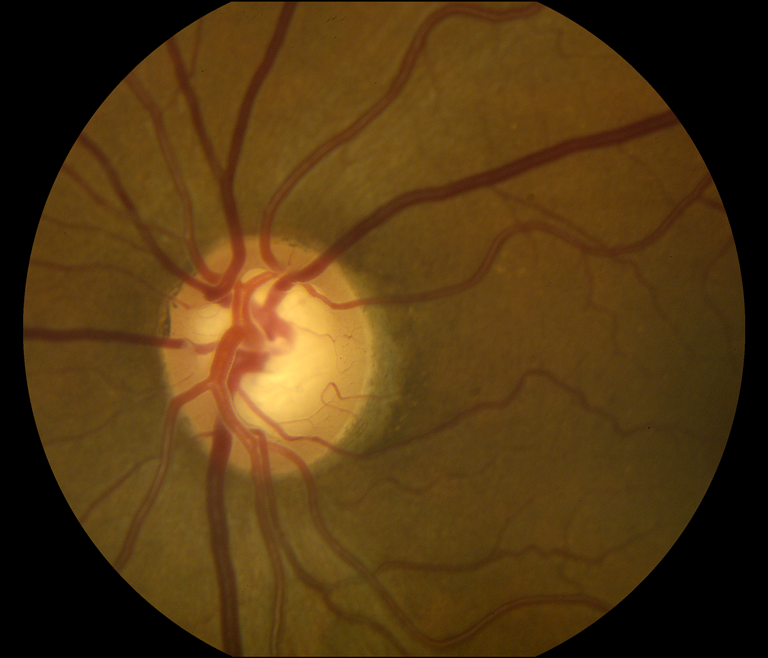

Optic Nerve Cupping

Presented by Lacee Cooper, BA, COA, CRAThis photograph received Honorable Mention in the category "Fundus Photography, High Magnification, 20°" and was displayed at the 2024 ASCRS/OPS Society Exhibit.